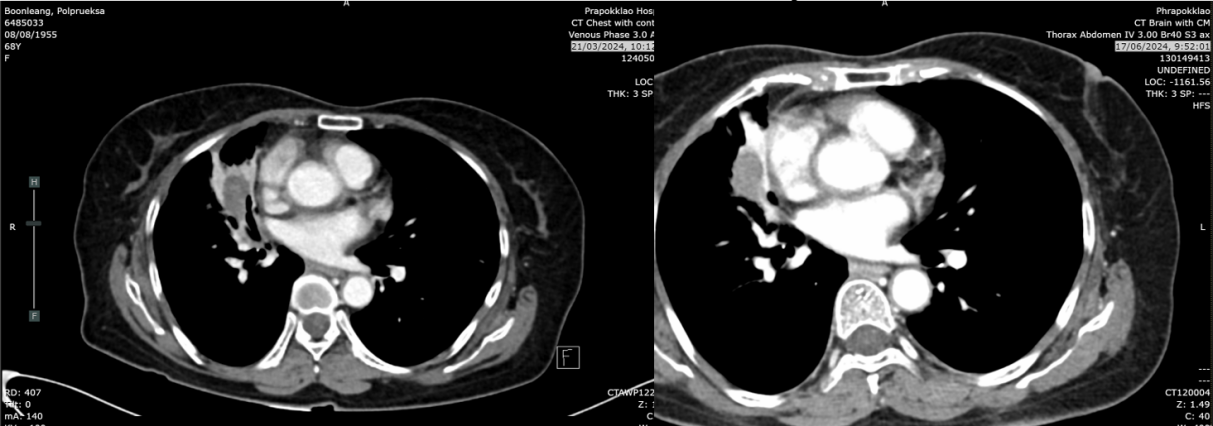

2024年3月21日:肿块缩小至2.8cm,实变及结节较前减少,考虑肺转移灶部分消退。

2024年6月17日:肿块略增至2.9cm,亚厘米级淋巴结。

2025年8月26日:肿块2.2cm,右肺上叶、中叶结节0.3-0.4cm稳定,中叶新增磨玻璃影(考虑感染或炎症),无新增转移灶。

疗效总结:自治疗开始计算,无进展生存期(PFS)达186周(3.5年);自停药后计算,PFS为102周(2年)。